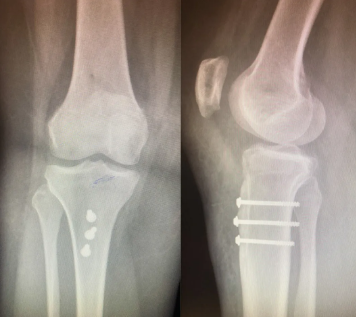

(3)胫骨结节内移

若存在胫骨结节外偏,需截骨内移并固定,调整髌骨力线。

(4)综合调整

在关节镜监视下,动态测试髌骨稳定性,确保无脱位倾向。